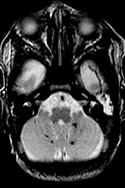

The Baby Brain Research Group studies how newborns' brains get injured and what the best diagnostic tools are to see that injury early on. Our aim is to see brain injury early enough so we can develop treatments to reduce the damage and aid recovery of injured areas. We also hope to identify those children whose long-term development will be affected, and who could benefit from early therapy.